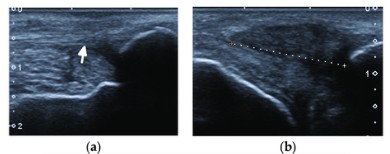

Esta otra imagen en eje corto permite contrastar la salud frente a la rotura total en un mismo paciente:

En la imagen (a), vemos el tobillo sano como referencia. El tendón (flecha) muestra su apariencia normal: un bloque ecogénico, brillante y con su estructura fibrilar intacta. Es el patrón de «normalidad» que hemos descrito al principio del artículo.

En la imagen (b), tomada al mismo nivel en el tobillo afecto, se aprecia la rotura completa. El tendón (delimitado entre los calibradores) aparece notablemente engrosado y muy oscuro (hipoecoico).

Esta pérdida absoluta de la arquitectura fibrilar y el cambio de tono indican una desorganización total del tejido tras la rotura espontánea, marcando una diferencia visual clara con el lado sano.